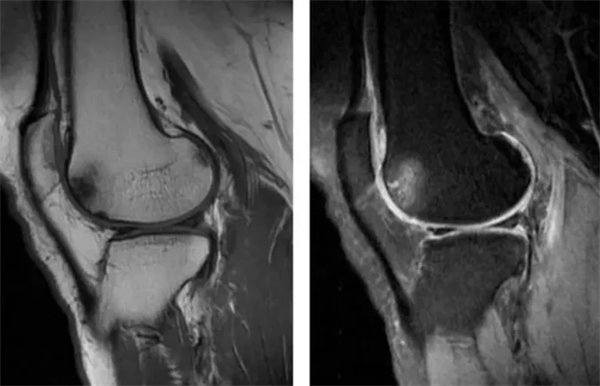

图1

常规T1WI,T2WI图,股骨外侧髁前、后部软骨下骨质呈斑片状长T1、长T2信号。

图2

常规T1WI,T2WI图,股骨外侧髁前部局部骨质呈小斑片状长T1、长T2信号,相应软骨信号未见异常。